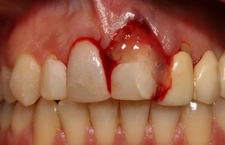

Diş ekimi, günümüzde oldukça yaygın bir işlem olmasına rağmen, her cerrahi müdahalede olduğu gibi bazı riskleri de beraberinde getirebilir. Enfeksiyon ve vücut reddi, bu işlemin potansiyel komplikasyonları arasında yer alır. Ancak, bu riskler uygun önlemlerle önemli ölçüde azaltılabilir.